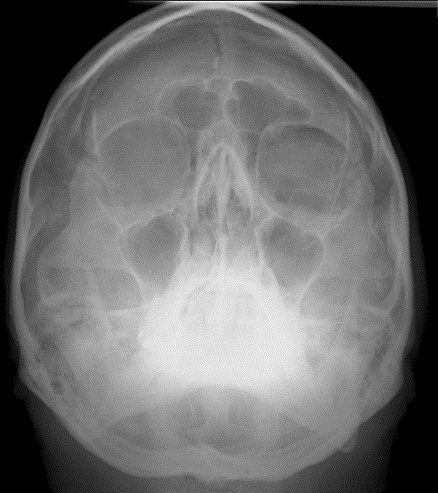

Radiograph of the black eyebrow sign[1], seen in pathologies such as Orbital Emphysema

Bickle I, Black eyebrow sign - orbital blow-out fracture. Case study, Radiopaedia.org (Accessed on 04 Jul 2024) https://doi.org/10.53347/rID-22525